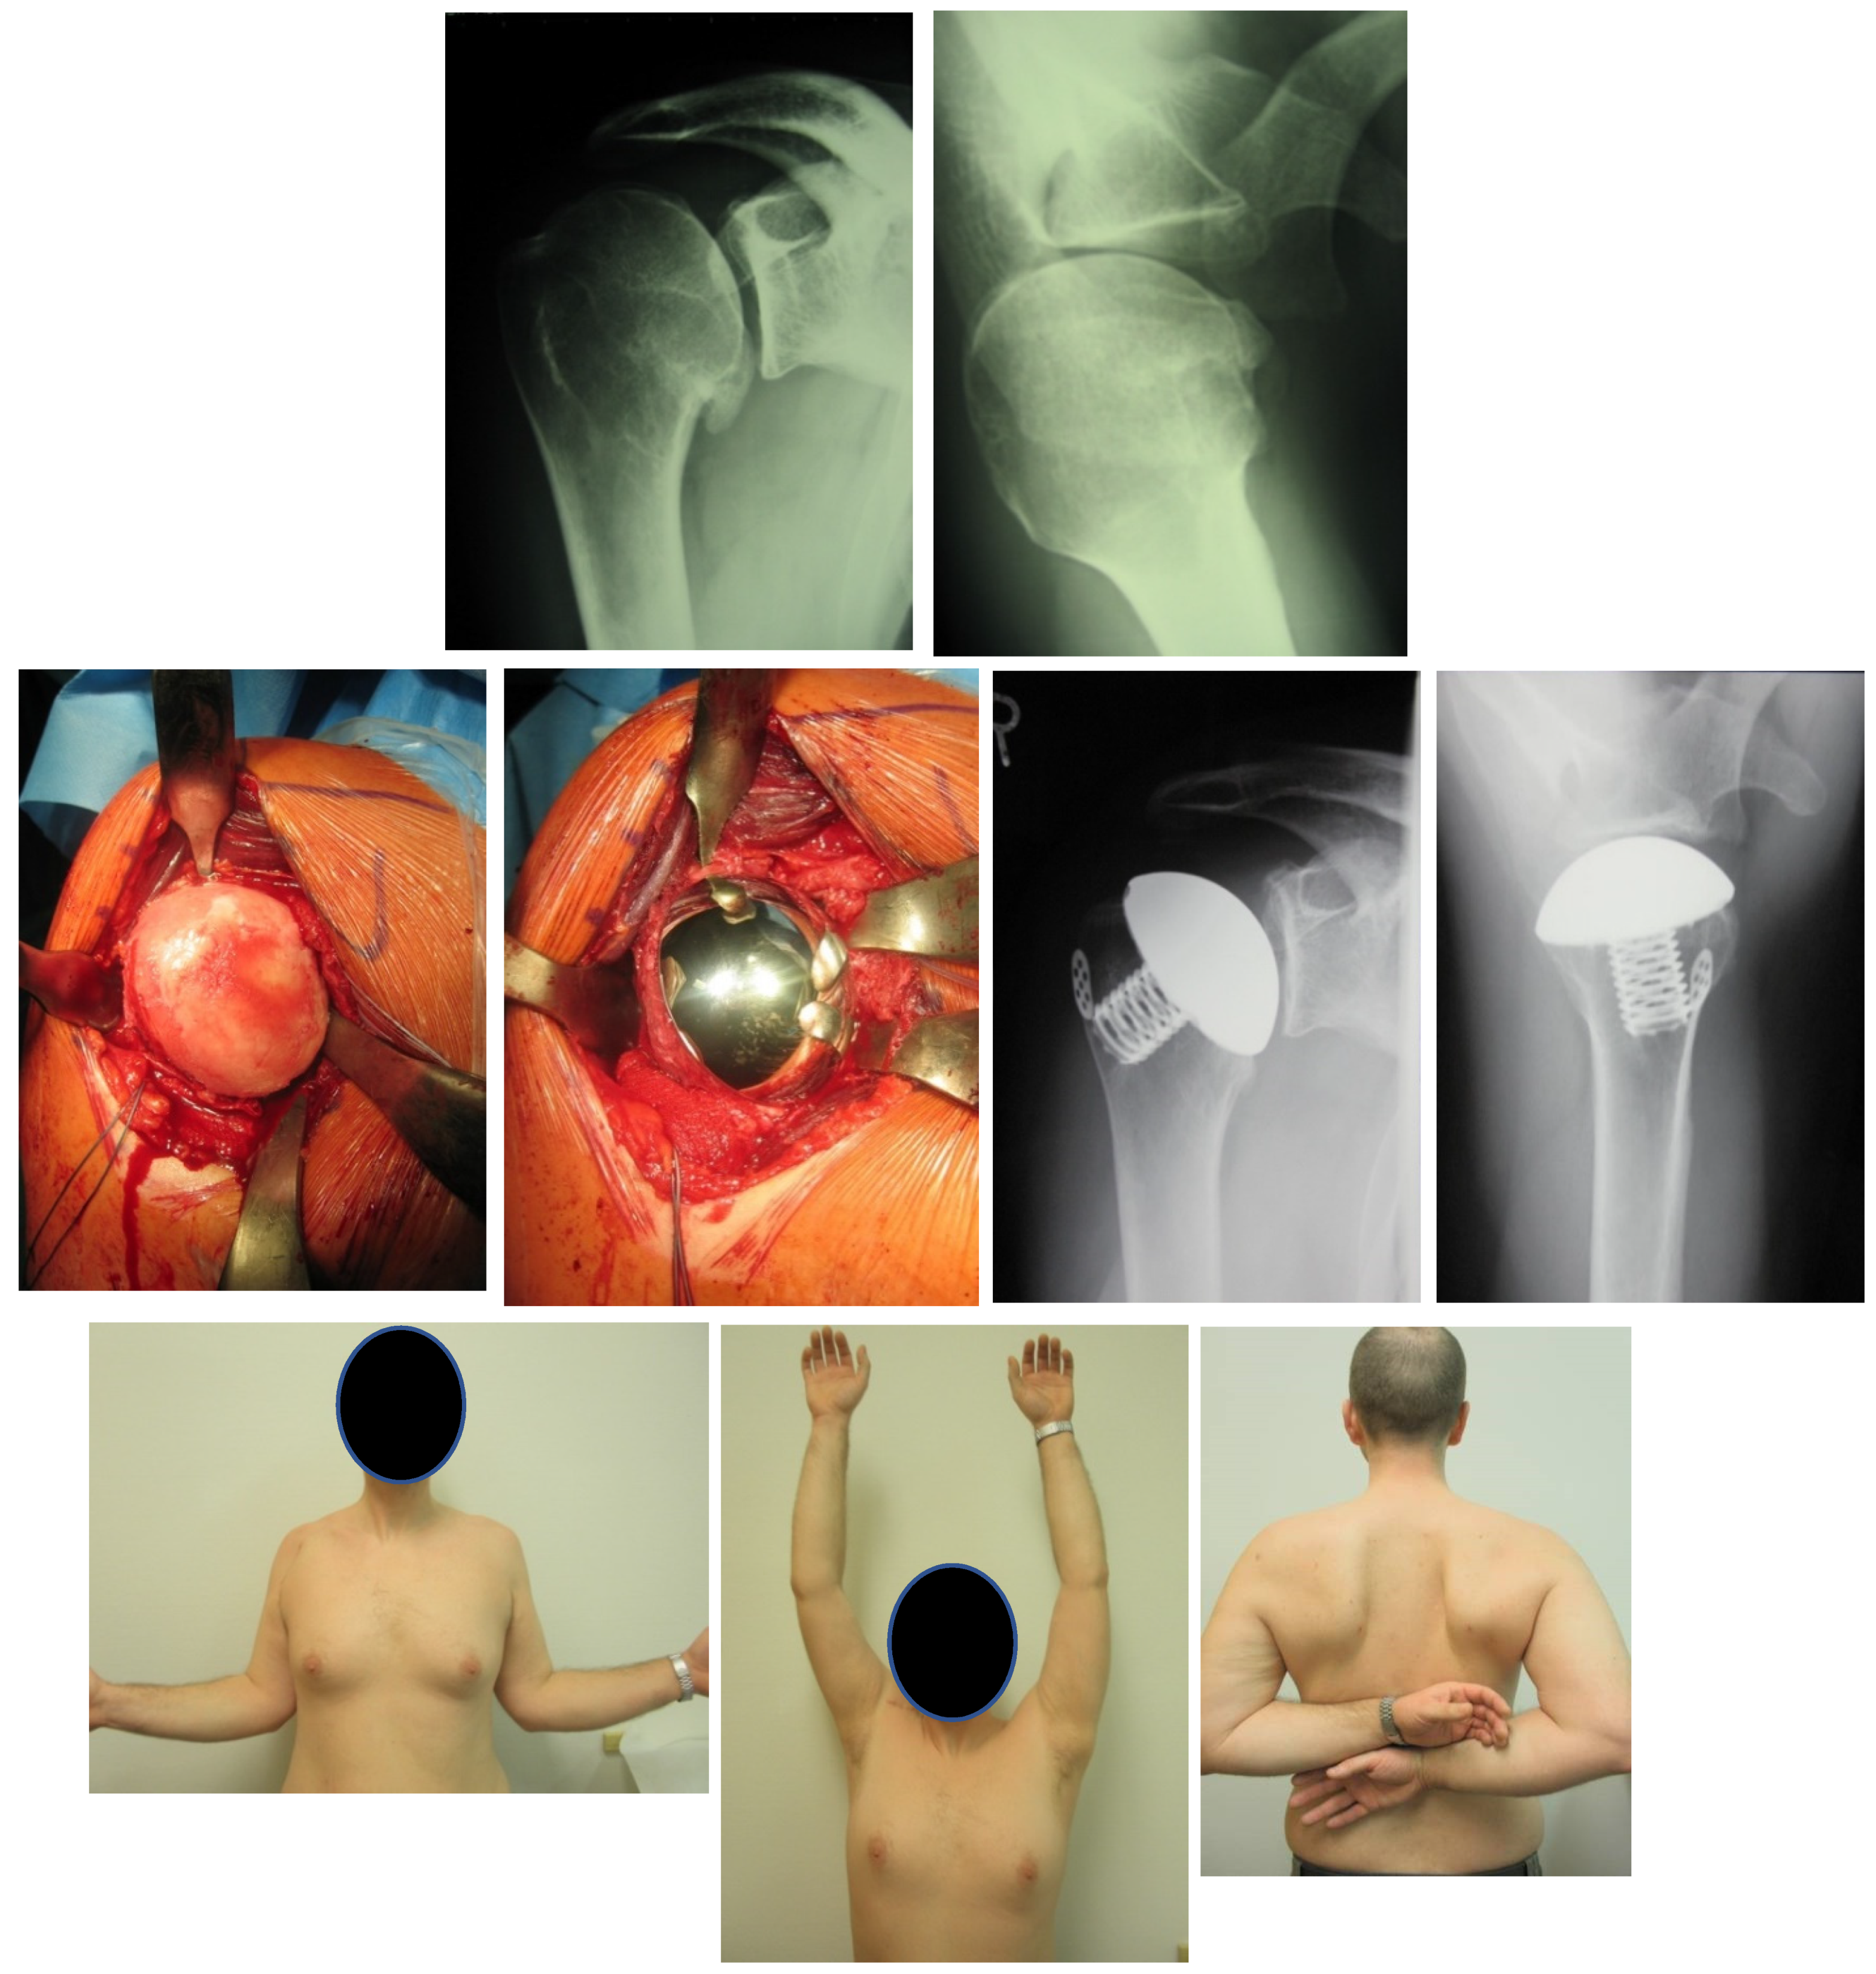

6.4. Arthroplasty

Results after Arthroplasty

- Lehmann, L.; Magosch, P.; Mauermann, E.; Lichtenberg, S.; Habermeyer, P. Total Shoulder Arthroplasty in Dislocation Arthropathy. Int. Orthop. 2010, 34, 1219–1225. [Google Scholar] [CrossRef] [PubMed] [Green Version]

- Habermeyer, P.; Lichtenberg, S.; Magosch, P.; Baierle, T. (Eds.) Schulterchirurgie: Mit dem Plus im Web; Zugangscode im Buch; 4. Aufl.; Elsevier, Urban & Fischer: München, Germany, 2010; ISBN 978-3-437-22341-9. [Google Scholar]

- Pape, G.; Raiss, P.; Aldinger, P.R.; Loew, M. Comparison of short-term results after CUP prosthesis with cemented glenoid components and total shoulder arthroplasty: A matched-pair analysis. Z. Orthop. Unf. 2010, 148, 674–679. [Google Scholar] [CrossRef] [PubMed]

- Neer, C.S.; Morrison, D.S. Glenoid Bone-Grafting in Total Shoulder Arthroplasty. J. Bone Jt. Surg. Am. 1988, 70, 1154–1162. [Google Scholar] [CrossRef]

- Sperling, J.W.; Antuna, S.A.; Sanchez-Sotelo, J.; Schleck, C.; Cofield, R.H. Shoulder Arthroplasty for Arthritis after Instability Surgery. J. Bone Jt. Surg. Am. 2002, 84, 1775–1781. [Google Scholar] [CrossRef] [PubMed]

- Matsoukis, J.; Tabib, W.; Guiffault, P.; Mandelbaum, A.; Walch, G.; Némoz, C.; Edwards, T.B. Shoulder Arthroplasty in Patients with a Prior Anterior Shoulder Dislocation. Results of a Multicenter Study. J. Bone Jt. Surg. Am. 2003, 85, 1417–1424. [Google Scholar] [CrossRef] [Green Version]